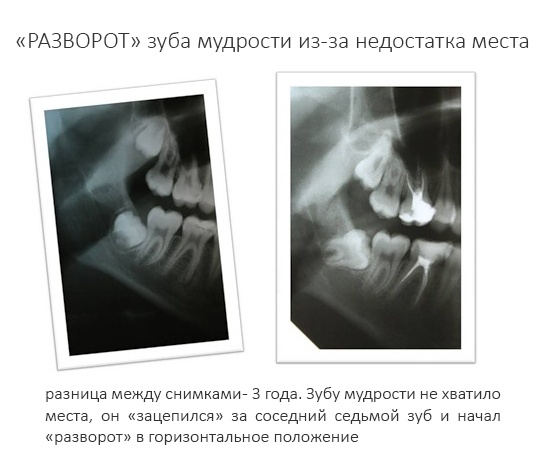

Так уж сложилось, что они начинают расти в тот период, когда активный рост челюстных костей замедляется, а зубной ряд, вроде как, уже «укомплектован». Зуб растёт вверх (или вниз, если на верхней челюсти), натыкается на препятствие в виде уже прорезавшейся семёрки, останавливается или начинает разворот.

Так получаются не только ретинированные (непрорезавшиеся), но и аномально расположенные (дистопированные) восьмёрки.